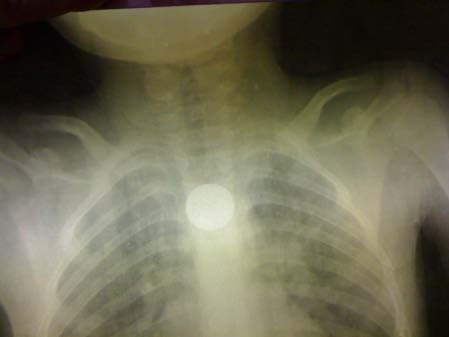

Front and side cervical radiography visualized the presence of a foreign body (coin) at the upper part of the esophagus in 28 children (80%), at the middle part of the esophagus in 05 cases (14 , 2%) and twice the foreign body was in the distal esophagus. (Fig. 2 The part was extracted on the 1 st attemptin 80.6%, on the second attemptin 11.3% and on the third attempt in 1.6% of the remaining cases. The median extraction time for the coin was 1 minute, ranging from 35 to 80 seconds, the median duration of sedation was 10 minutes. No complications related to endoscopic treatment were observed. Or even the anestheticact. All the children were monitored for 02 hours in the recovery room and redirected to the ENT service. The children whose EC was viewed at the ASP had benefited from the control ASPs performed at the ENT service, remotely from the acute episode and which showed the progression of the EC along the digestive tract until its expulsion by natural way.